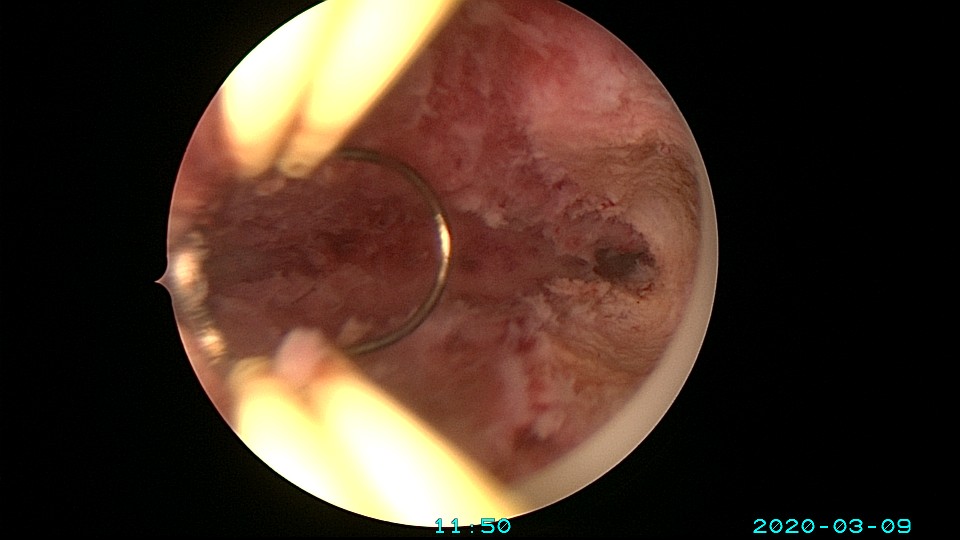

患者36岁,G3P0,自然流产3次,发现宫腔粘连3个月。2020年3月宫腔镜探查,子宫前倾后屈位,宫深8.5cm,宫颈管粘连狭窄,扩宫进入宫腔,见宫腔中下段两侧壁粘连,剪刀及双极电切分粘,宫腔形态恢复正常,双侧输卵管开口显露。2020年4月宫腔镜二探取球囊,宫腔形态正常,双侧输卵管开口可见。2021年6月自然妊娠,2022年2月足月剖宫产分娩。现42岁,G4P1。